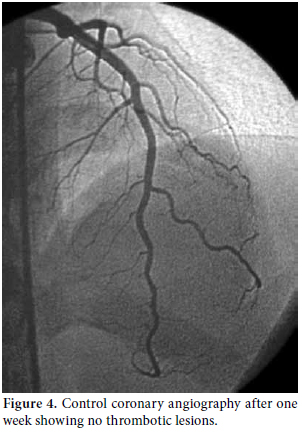

During the clinical follow-up period, the patient's ECG showed dynamic anterior ST-T changes in the precordial derivations (Figure 1), and repeat measurements of these markers revealed a typical course of ACS that featured a relevant rise and fall in TnI. Therefore, the patient underwent coronary angiography which revealed a distally occluded left anterior descending coronary artery (Figure 2). Percutaneous transluminal coronary angioplasty was performed on the occluded site, and because of the thrombotic view of the lesion with a remnant of 30% stenosis accompanied by thrombolysis in myocardial infarction (TIMI) three flow, medical therapy with tirofiban infusion was prescribed for up to a period of 24 hours instead of stent implantation.

Consultations were then held with the pulmonary medicine and rheumatology departments regarding the eosinophilia identified in the CBC, pulmonary opacities revealed via chest X-ray, and the patient's past history of asthma (Figure 3). Furthermore, cranial computed tomography (CT) was performed on the day after the angiography which showed neurological involvement or paranasal sinus abnormality with a prediagnosis of CSS. The results of the cranial CT were also consistent with chronic sinusitis. The presence of asthma, hypereosinophilia of >10%, chronic sinusitis, and pulmonary opacities represent four of the six ACR criteria required for the diagnosis of CCS.[5] Our patient tested negative for anti-nuclear antibodies (ANAs), anti-double stranded DNA (antidsDNA), extractable nuclear antigens (ENAs) and anti-neutrophil cytoplasmic antibodies (ANCAs). The corticosteroid methylprednisolone at an initial dosage of 80 mg per day (1 mg/kg/d) was prescribed after the termination of the tirofiban infusion. Afterwards, the patient's eosinophil levels in the CBC decreased to normal ranges, and symptomatic relief was completely provided. Control coronary angiography was performed one week later, and the thrombotic lesions had disappeared (Figure 4). In addition, chest radiographs showed complete resolution of the opacities (Figure 5). After two more weeks, control echocardiography was performed revealing a normal morphology of the ventricles without any segmental wall motion abnormalities. Furthermore, the pericardial fluid had also disappeared.